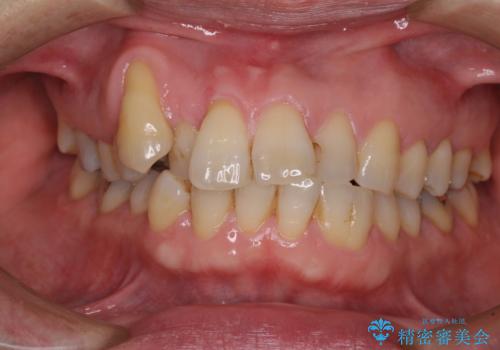

八重歯と形の悪い前歯 矯正治療とセラミック治療